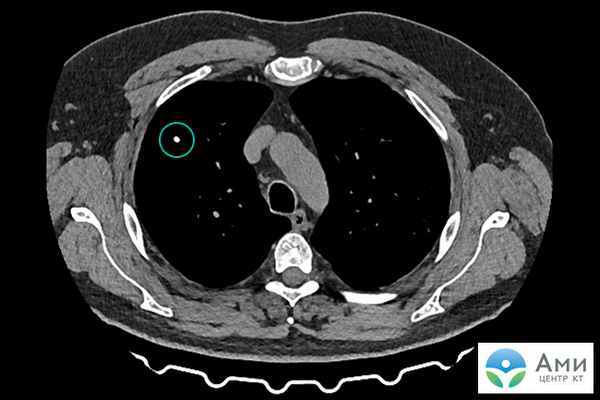

Кальцинат

Кальцинаты — патологические, как правило шарообразные, скопления солей кальция в тканях и органах. На сканах компьютерной томографии визуализируются как белые точки. Небольшие конкрементоподобные новообразования в молочной железе, легких, мягких тканях, артериях в большинстве случаев не причиняют дискомфорт и являются «случайными находками» на КТ, УЗИ, маммографии.

Кальцинаты не опасны, поскольку сами по себе не являются злокачественным новообразованием, однако могут быть «маркером» онкологического процесса, поскольку для очагов кальцификации характерна локализация рядом с опухолью и метастазами. Даже единичный кальцинат, обнаруженный на КТ, может требовать дополнительного обследования, если рядом имеется подозрительное уплотнение.

Размеры кальцинатов варьируются от 1-2 мм (гранулярные, микрокальцинаты, кальцинаты) до крупных (макрокальцинаты). Макрокальцинаты почти всегда доброкачественны и не требуют дальнейшего наблюдения.

Кальцинаты на КТ визуализируются даже при самом небольшом размере капсулы (около 1 мм).